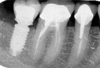

Fracture de la deuxième molaire

Il a été possible d’assurer au patient que l’origine de son infection était une fracture au niveau de sa deuxième molaire en raison de la forme de l’infection et du sondage parodontal.

Dans ce cas, la fracture est ancienne et l’infection a créé une perte osseuse importante à la radiographie. L’extraction est programmée mais l’implantation est différée dans le temps. En effet, les fractures anciennes peuvent constituer un réservoir bactérien dans l’os, ce qui est souvent à l’origine d’un échec implantaire. Il est alors « urgent d’attendre » dans ces cas (de 6 à 12 mois selon les cas) avant d’implanter.